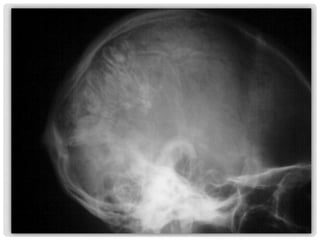

Hallazgo radiológico en

proyecciones simples de

cráneo, AP y lateral, en

paciente masculino de 22

años con cefalea, sin mas datos

clínicos en su solicitud médica.

PROYECCIONES

RADIOLÓGICAS

SIMPLE,

INICIALES.

Las radiografías simple de cráneo

muestran calcificaciones

intracraneanas con patrón

giriforme, proyectadas en

topografía del hemisferio cerebral

izquierdo.